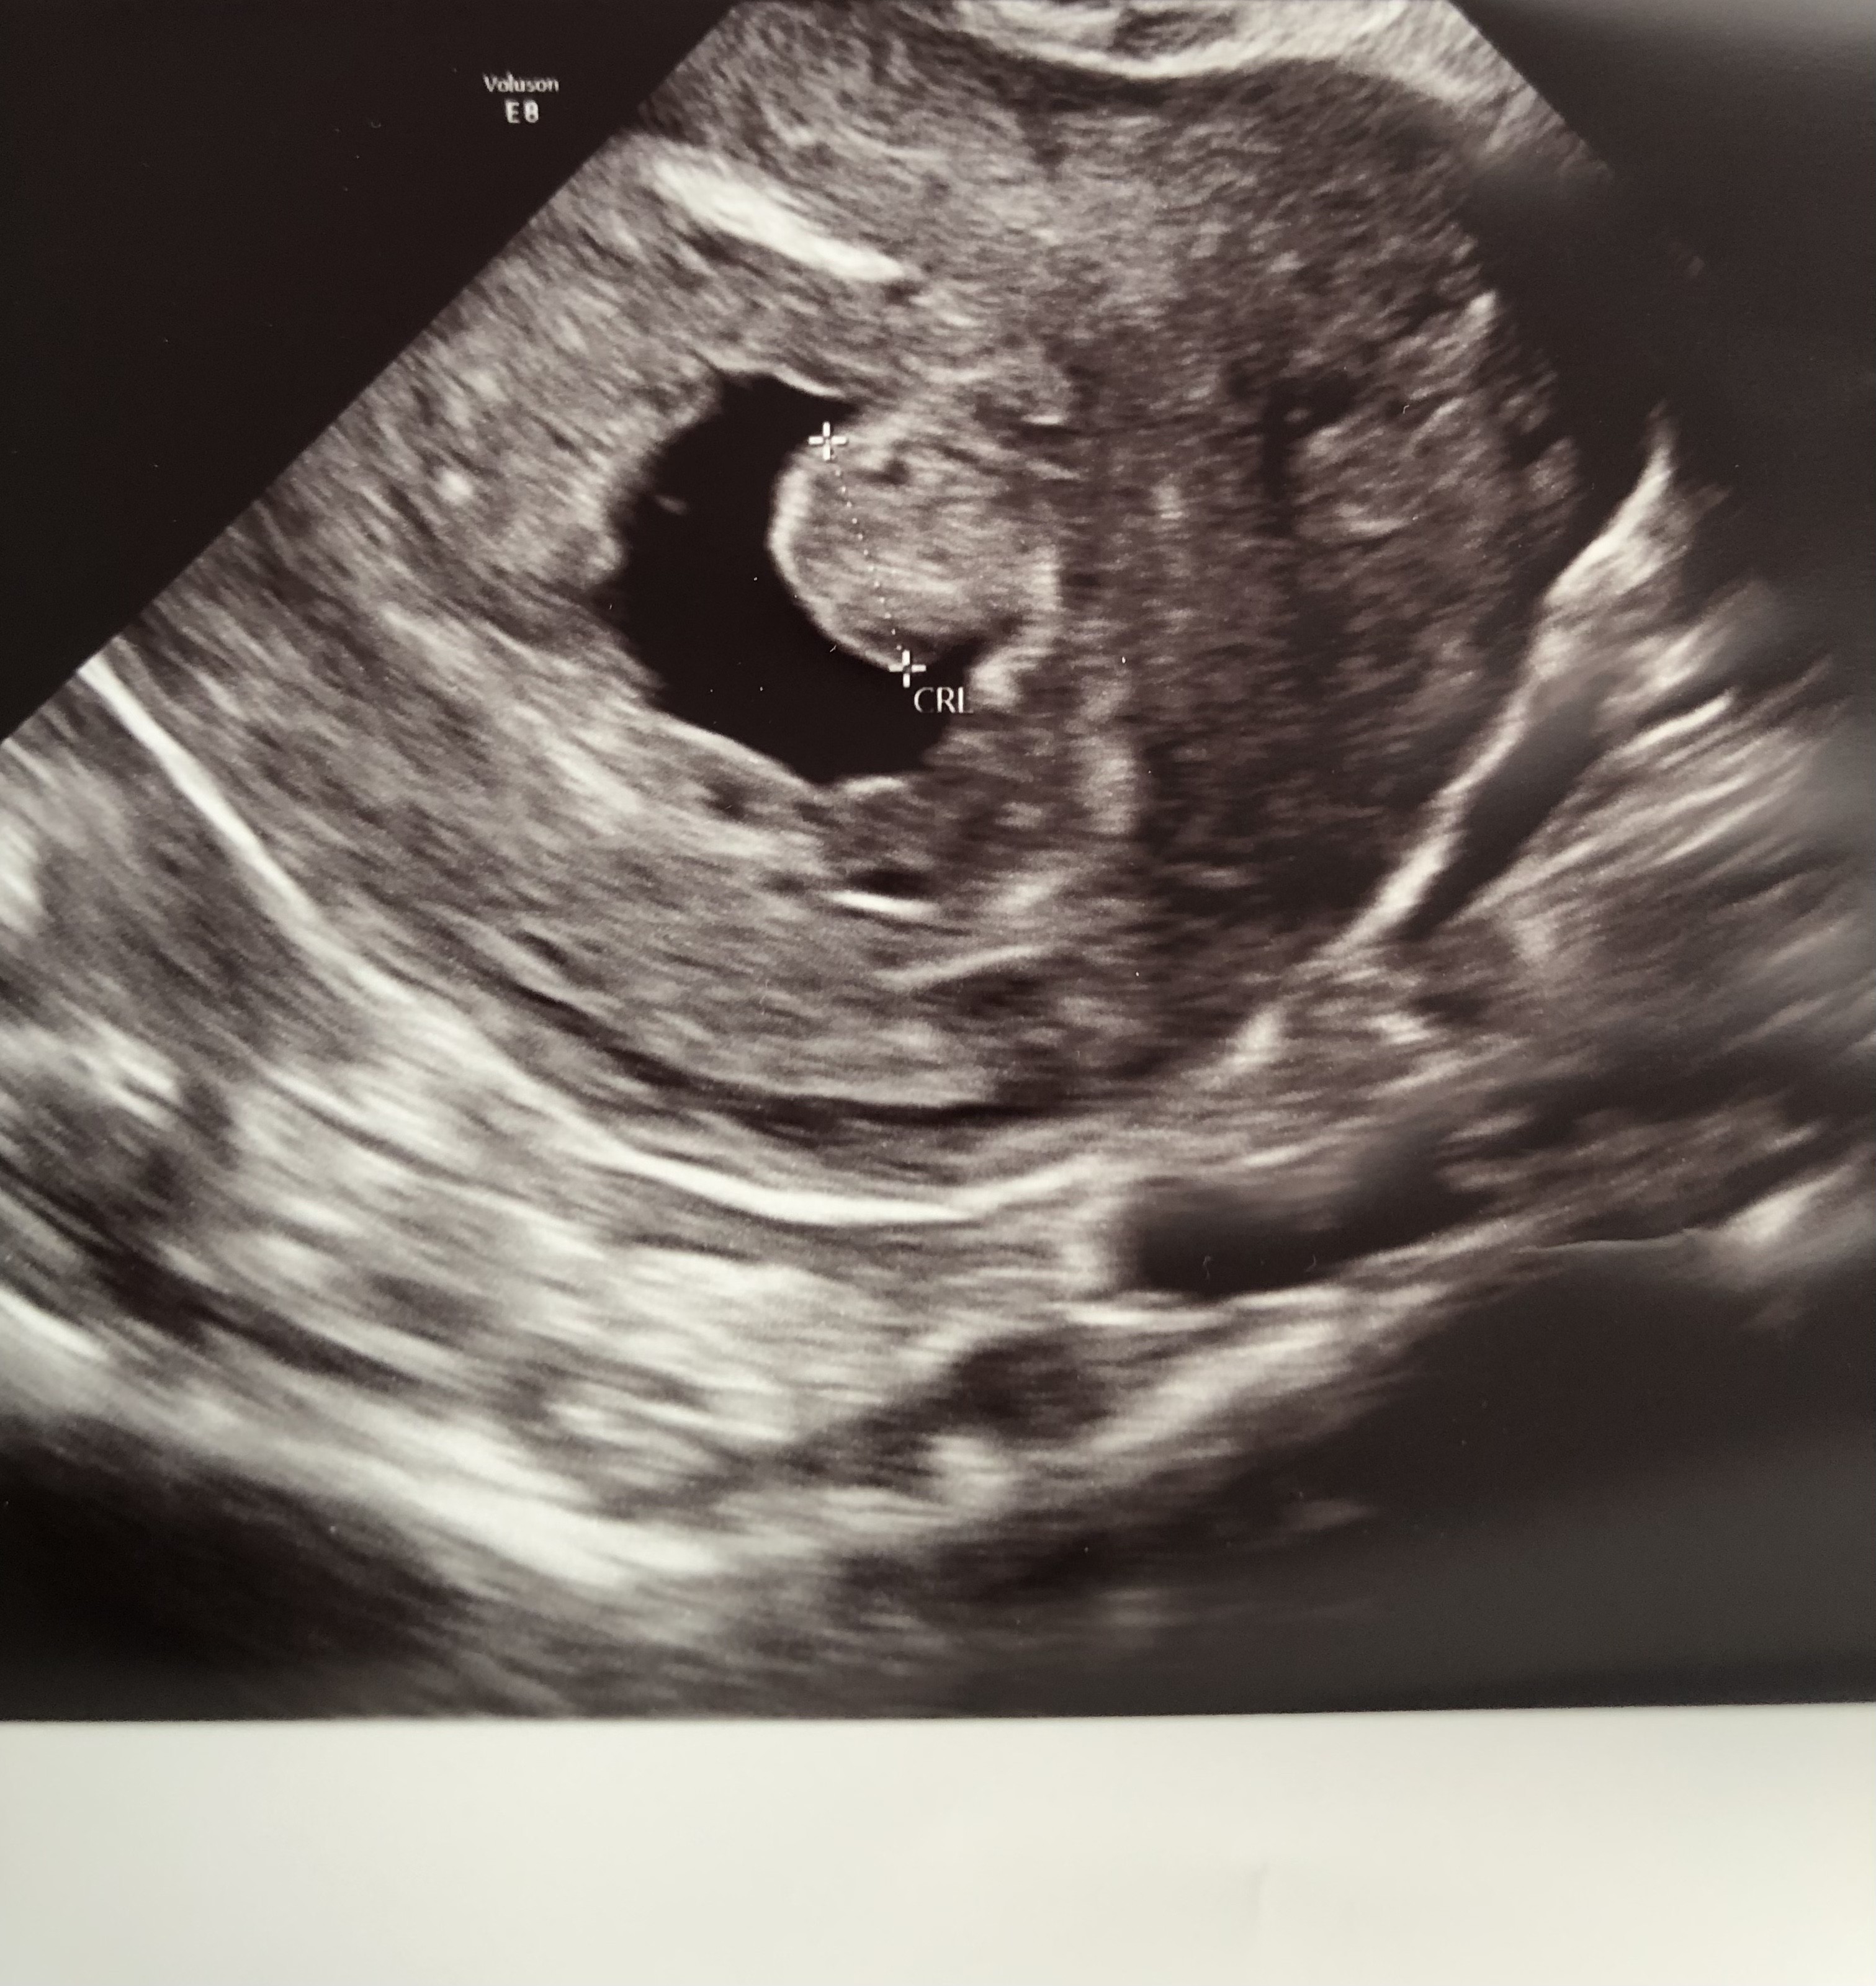

Czy będzie zarodek z bijącym sercem?

Hej,

Z OM wychodzi 7 tydzień 3 dzień. Ginekolozka powiedziała, ze ciąża wyglada dziwnie, ze nic z tego nie będzie i dała skierowanie do szpitala z podejrzeniem poronienia zatrzymanego. Kazała przyjść za tydzień na usg. Czy naprawdę nie ma już szans?

@Lily123 , obawiam się, że kiepsko to wygląda.

Mój osobisty zarodek stracił tętno przy 10 mm. Wcześniej je miał. W necie piszą o serduszku już w 6 tygodniu, na 3 mam dzidzi. :( Twoja ma 94 mm... Przykro mi bardzo. W mojej opinii masz bardzo nikłe szanse na szczęśliwe zakończenie. ;(